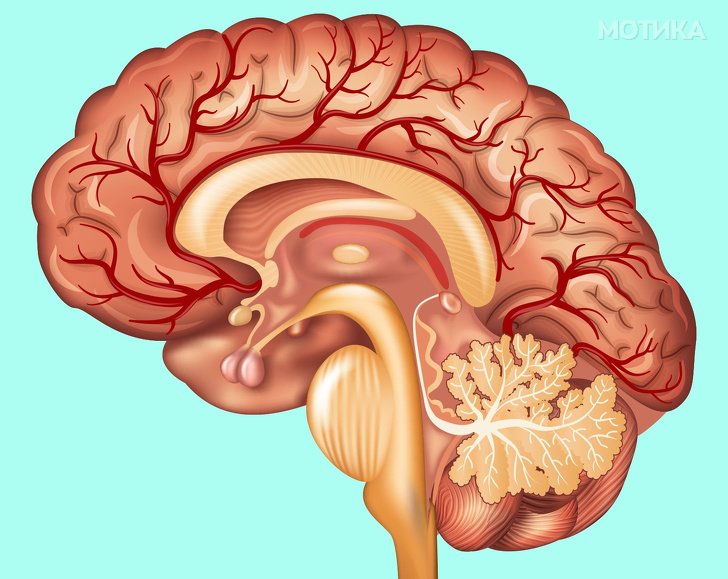

9. Мозок

- Мозокот е можеби единствениот орган чија функција е уште малку мистерија. Тој содржи околу 100 милијарди неврони.

- Мозокот нема рецептори за болка, со други зборови, може да ги толкува сигналите за болка, но не може да чувствува болка.

- Мозокот има меморија од околу 100 терабајти што го прави супер-компјутер.

- За жал, мислењето дека ние користиме само мал дел од својата способност на мозокот е само мит, ние го користиме со полн капацитет, всушност дури и користиме околу 10% кога спиеме.